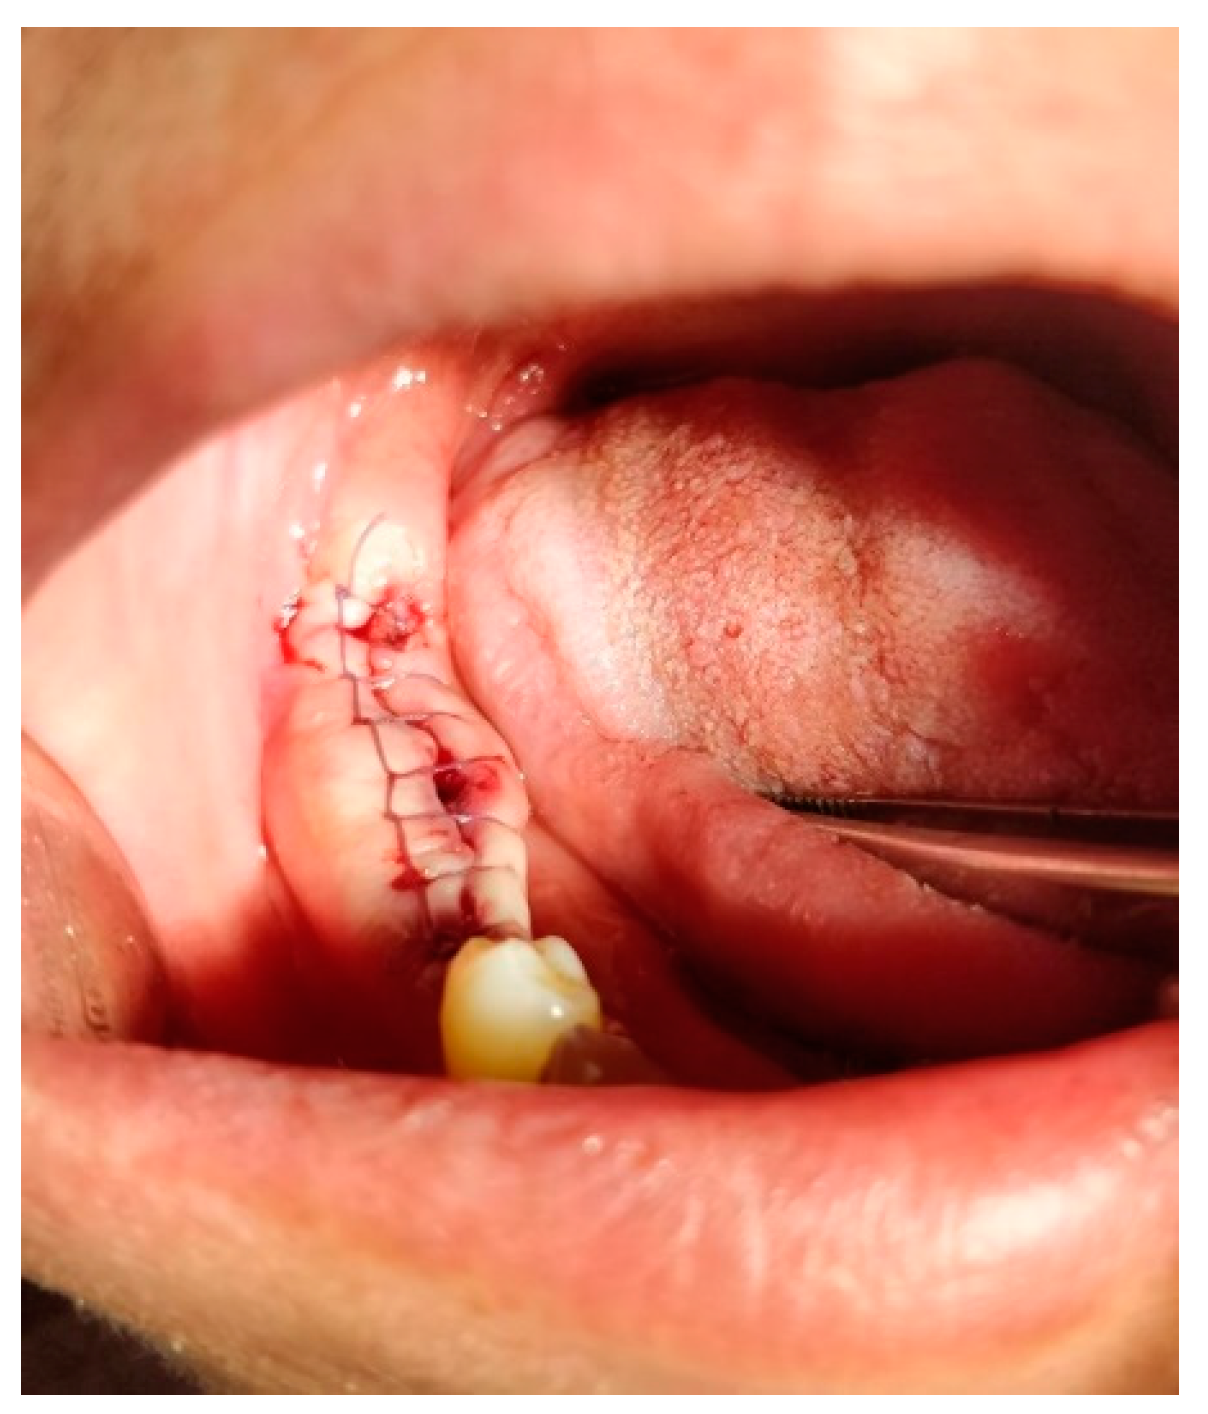

17. Surgical Suturing (Sutura Chirurgica)

- Single Throw Knot (One-Loop Knot, Figure 28)

- Square Knot (Simple Knot, Granny Knot, Figure 28):

- Surgeon's Knot (Two-Handed Knot, Double Throw Knot, Figure 28):